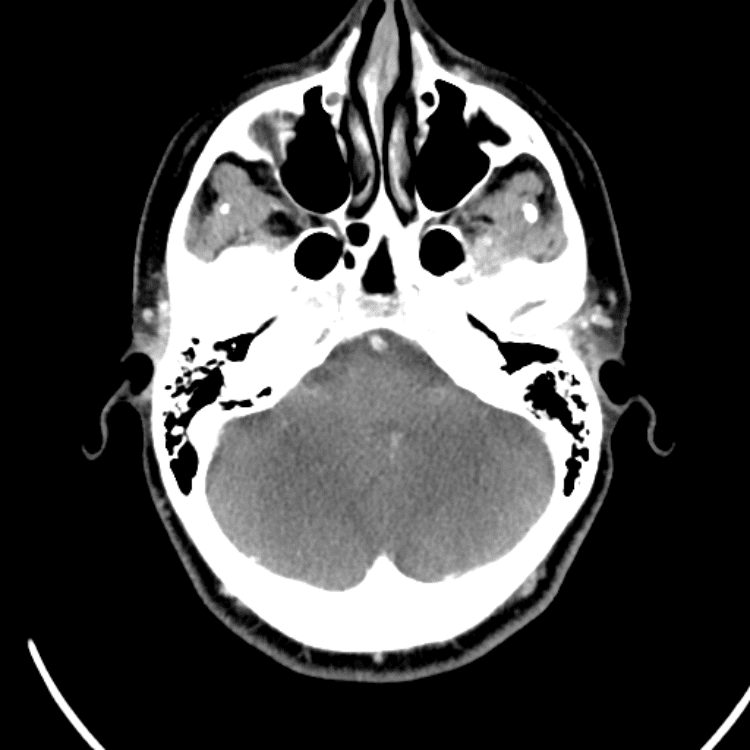

Head and Neck

Practice

Simulates call by including subtle or difficult cases and some normals.

27 cases